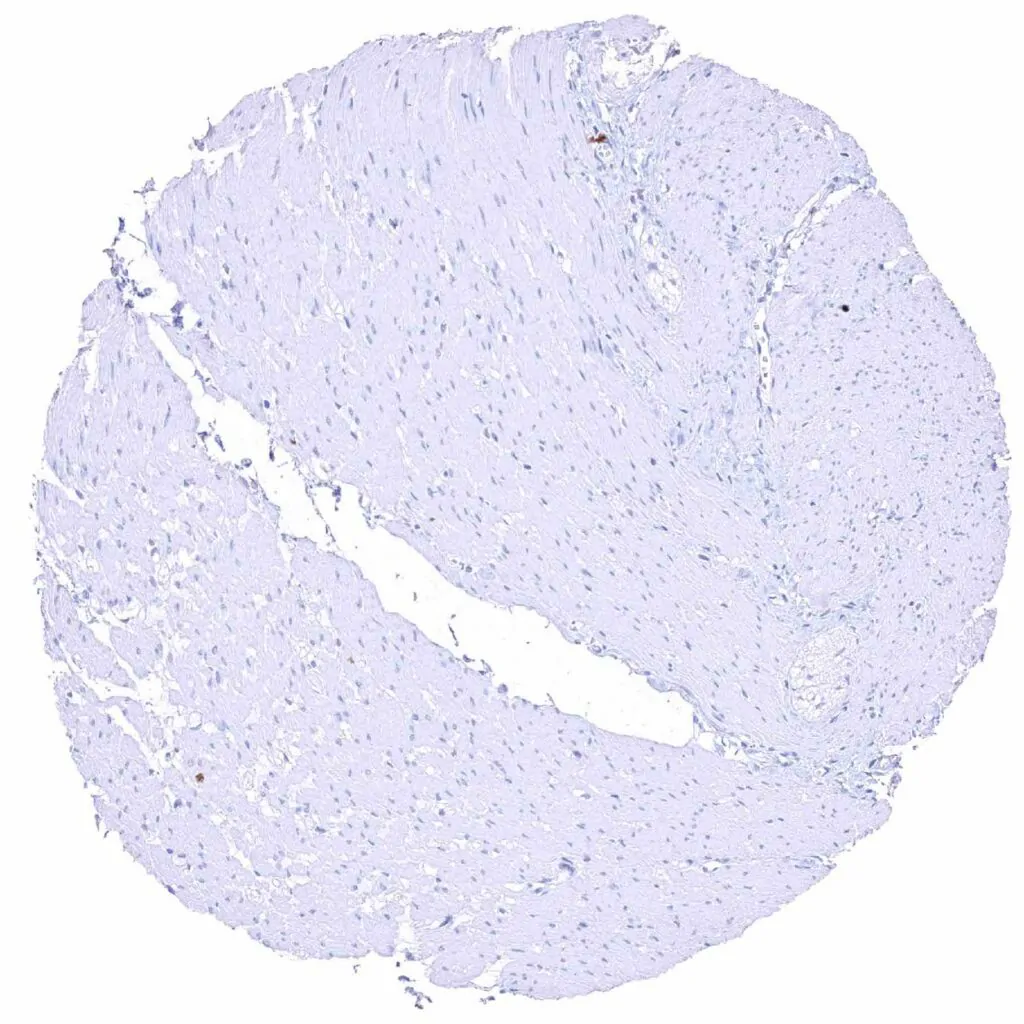

Heart muscle – Strong cytoplasmic MYH7 staining of all muscular cells